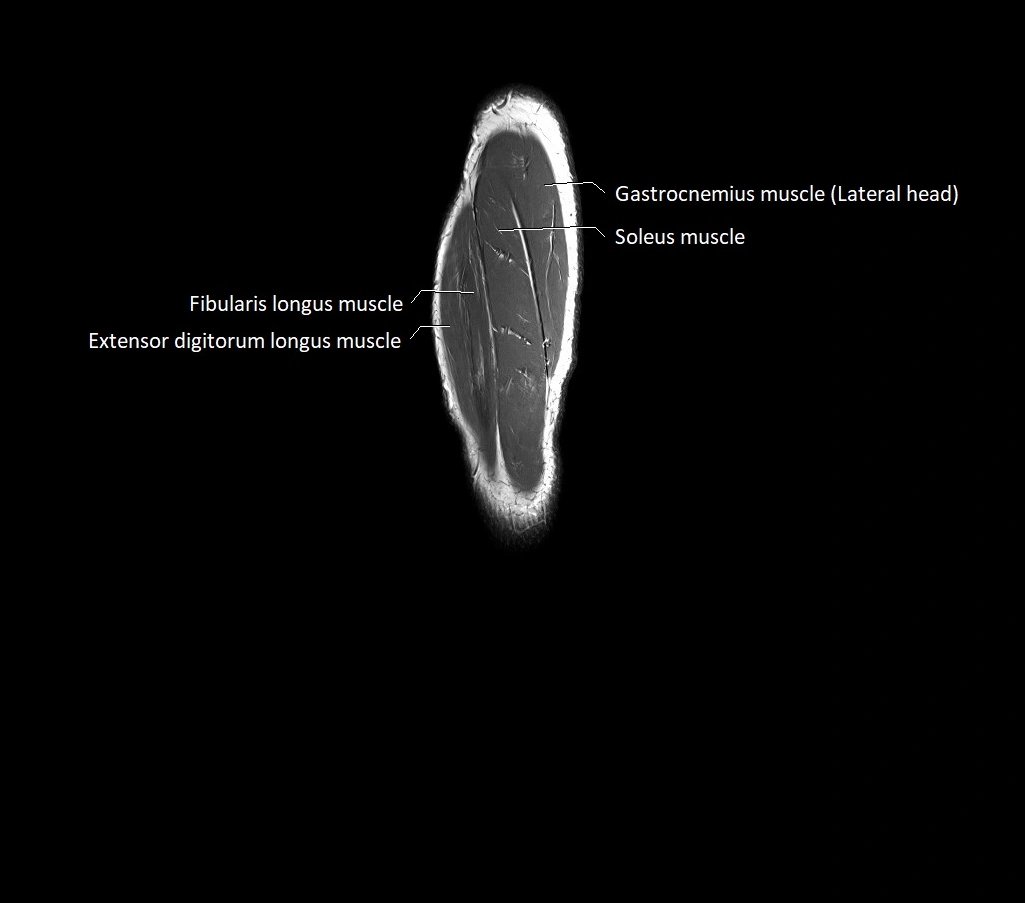

MRI image